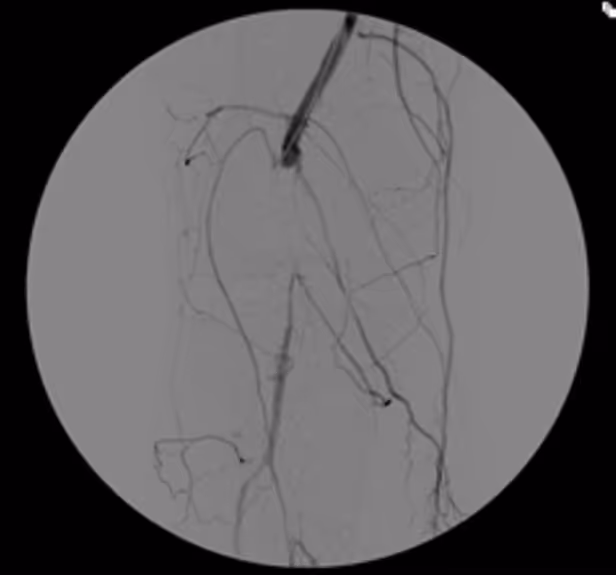

Many peripheral stenoses and occlusions are accessible by endovascular means. Among the endovascular procedures treatment of iliac and femoro-popliteal stenoses/occlusions are the most often used techniques. Thorough planing, proper use of endovascular tools and adherence to meticulous endovascular techniques are therefore of upmost importance for the success.